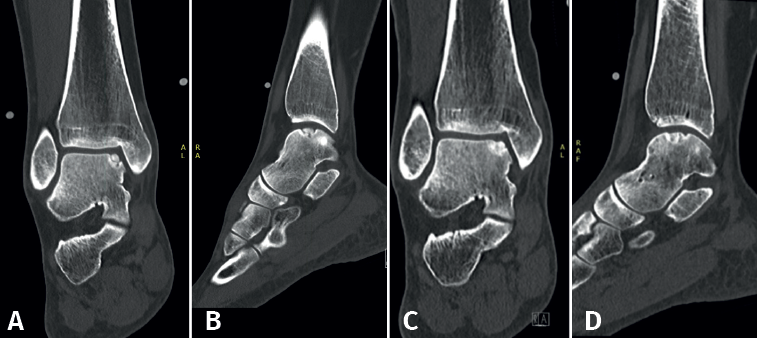

Further imaging can be deployed when there is a clinical suspicion for an OLT. Radiographs can be useful for assessing the ankle alignment but have a low diagnostic value in OLTs(8). Radiological confirmation and evaluation of OLTs should be conducted using computed tomography (CT) scans and/or magnetic resonance imaging (MRI), which have high diagnostic sensitivity and specificity(8,9). MRI can be useful to assess the ankle cartilage, detect bone marrow edema, or diagnose concomitant soft tissue injuries of the ankle. However, CT is preferred to assess the bony morphology and size of OLTs and to assess the subchondral bone layer, because MRI can overestimate lesion size due to the bone edema(9,10). Additionally, CT is a valuable tool for the assessment of the subchondral bone layer, which plays a significant role for OLTs(7). CT is also useful in pre-operative planning, for instance the feasibility of reaching the OLT arthroscopically(11). Single-photon emission computed tomography (SPECT) combines CT-based assessment of lesion size and morphology with functional imaging of lesion activity(12,13). Thus, SPECT may be of added value in treatment decision-making in complex cases with co-existing pathology, to identify the main cause of symptoms when standard imaging and clinical evaluation fail to provide adequate diagnostic insight(9).

Lesions can be characterized by location, morphology, and size. Location can be described using a 9-grid anatomical scheme of the talus, as described by Raikin et al., shown in Figure 1(14). The morphology of OLTs can be described as crater-like, cystic, or fragmentary (Figure 2)(4,15,16). Lesion size should be reported in anterior-posterior plane, medial-lateral plane, and depth, allowing for calculation of lesion surface area and volume(4). However, there is no consensus on the reporting on morphology of OLTs, and while radiological classification systems for OLTs exist, they lack validation and utilize inconsistent terminology. Moreover, lesion size measurement methods vary, further contributing to inconsistency in lesion characterization in literature(15).